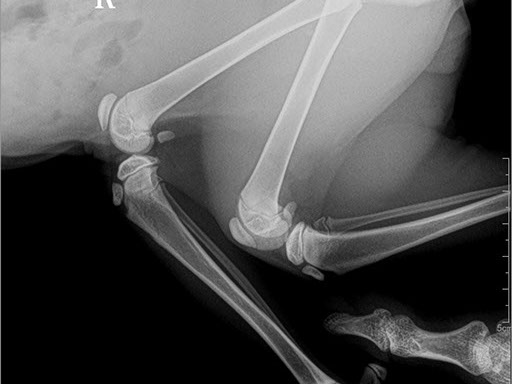

Коллиматорный прицел формирует пучок рентгеновского излучения на участок исследования. Проходя через ткани тела, излучение попадает на плоскопанельный цифровой детектор, который, в свою очередь, передает сигналы на компьютер.

В считанные секунды полученные данные обрабатываются компьютером посредством установленной на него программы визуализации, и сформированное клиническое изображение выводится на монитор лаборанта.